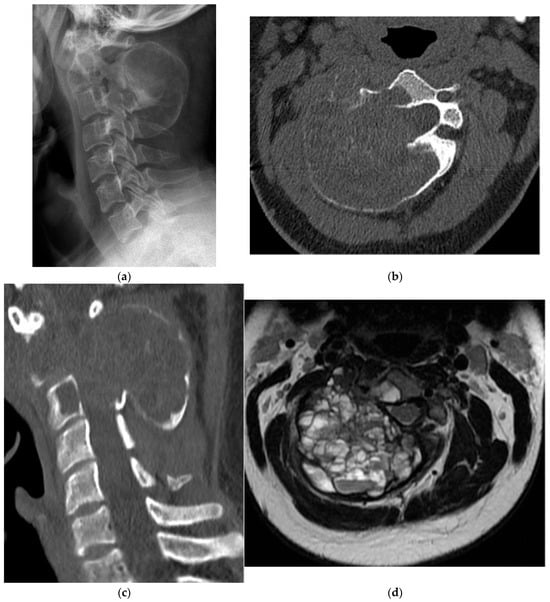

Paget’s Disease

Ewing Sarcoma

Langerhans Cell Histiocytosis